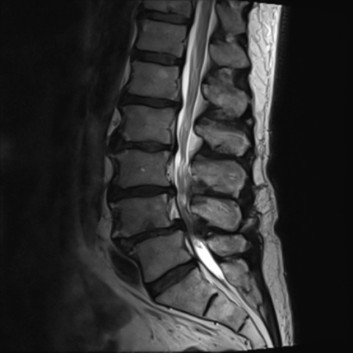

척추관 협착증의 치료

좁아진 척추관에 의해 발생한 협착증은 심한 경우 주사로 좁아진 공간을 넓게 할 수 없습니다. 다만 심부신경주사치료를 통해 척추관을 효과적으로 감압 할 수 있으며 신경에 대한 주변 조직의 압박을 줄이고 자극과 유착을 제거 합니다. 주사로 해결 되지 않는 경우 신경성형술 등의 시술을 고려 할 수 있으며 운동신경손상 및 통증 정도에 따라 수술을 시행 해야 하기도 합니다.